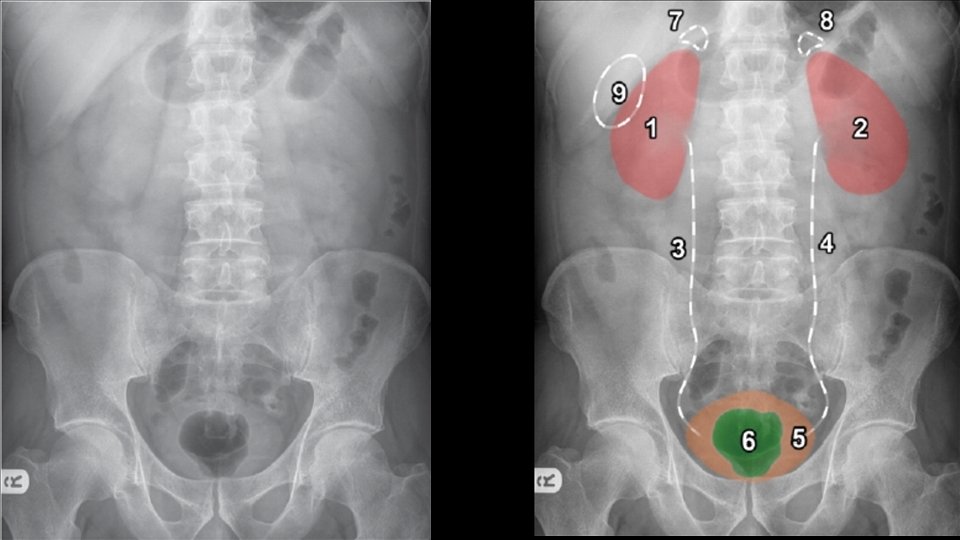

Abdominal viscera • Solid • • Liver Spleen Kidneys and adrenals Pancreas • Hollow • Stomach • Small bowel • Large bowel • Musculoskeletal parts

Urolithiasis Calculi along urinary tract • Anywhere • Kidney • Ureter • Bladder